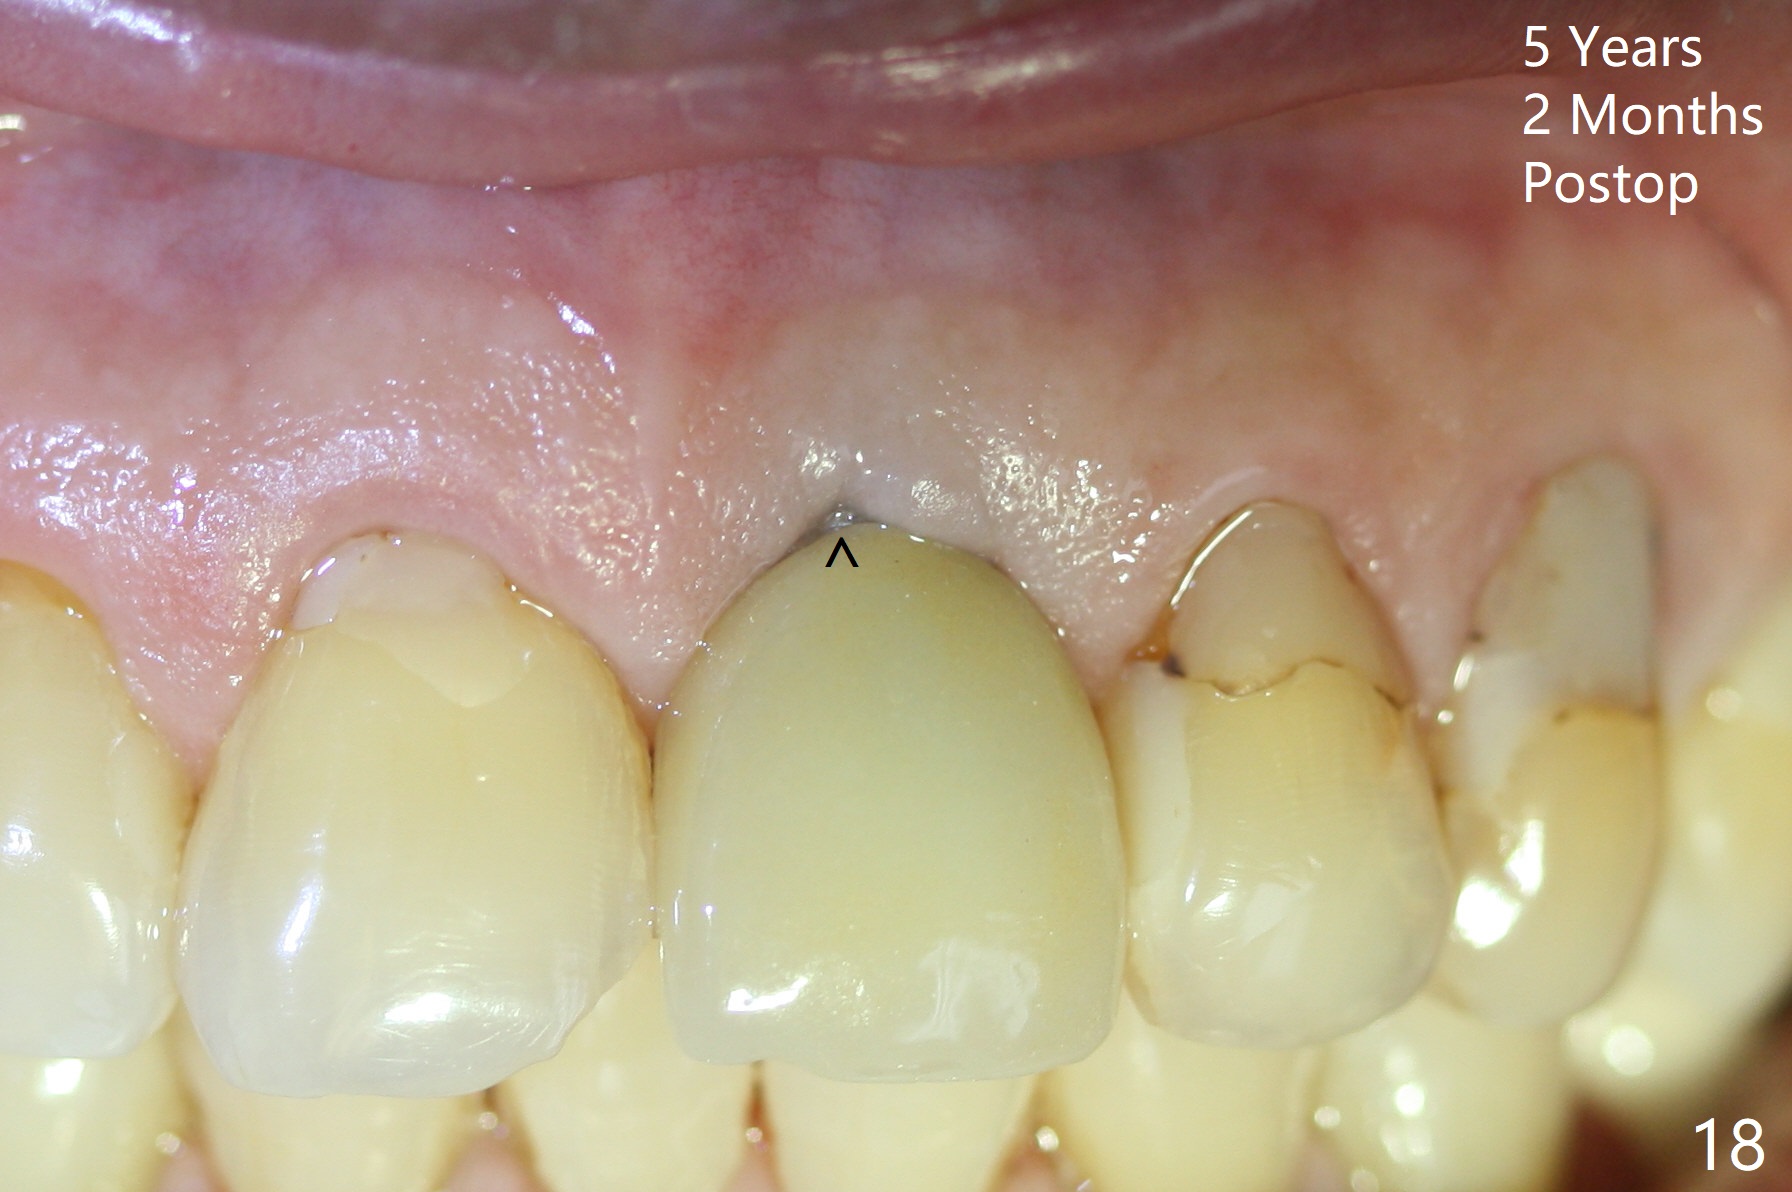

Postop tenderness lasts for two days. The palatal swelling is unnoticeable 7 days postop (Fig.9 *, as compared to A in Fig.8). The bone remains stable around the implant (Fig.10), while the gingiva healthy around the immediate provisional (Fig.11) 5 months postop. Due to insurance limit, the permanent restoration is delayed (16 months postop, Fig.12). The patient is satisfied with the function and appearance 3 years 8 months postop (21 months post cementation, Fig.13,14). PA is taken 4 years 1 month postop (2.5 years post cementation, Fig.15). The lamina dura forms from the most coronal threads (Fig.16). Although there is no bone loss around the implant (Fig.17), metal starts to show 5 years 2 months postop (Fig.18 ^), probably related to the buccal placement, too large the implant for the site or buccal plate atrophy (Fig.19).